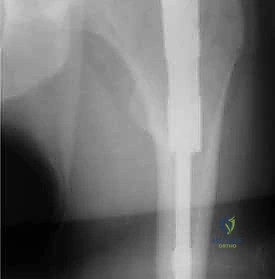

2. الأشعة السينية (X-Rays): هي المعيار الذهبي والأول للتشخيص. يتم أخذ صور من زوايا متعددة (أمامي خلفي وجانبي) لتحديد موقع الكسر، ونوعه، ودرجة تفتت العظام.

3. الأشعة المقطعية (CT Scan): يطلبها الدكتور هطيف في حالات الكسور المعقدة والمتفتتة جداً، حيث توفر صورة ثلاثية الأبعاد تساعد في التخطيط الجراحي الدقيق واختيار حجم المسمار المناسب.